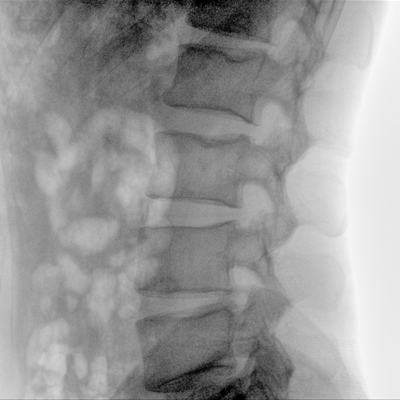

骨科: 经皮锥体成形术、经皮椎间盘臭氧治疗术、胸脊椎固定、骨活检、腰椎内固定术等。

优质平板探测器、可灵活升降调节SID、独特图像处理系统、高品质滤线栅,大视野成像清晰不失真。